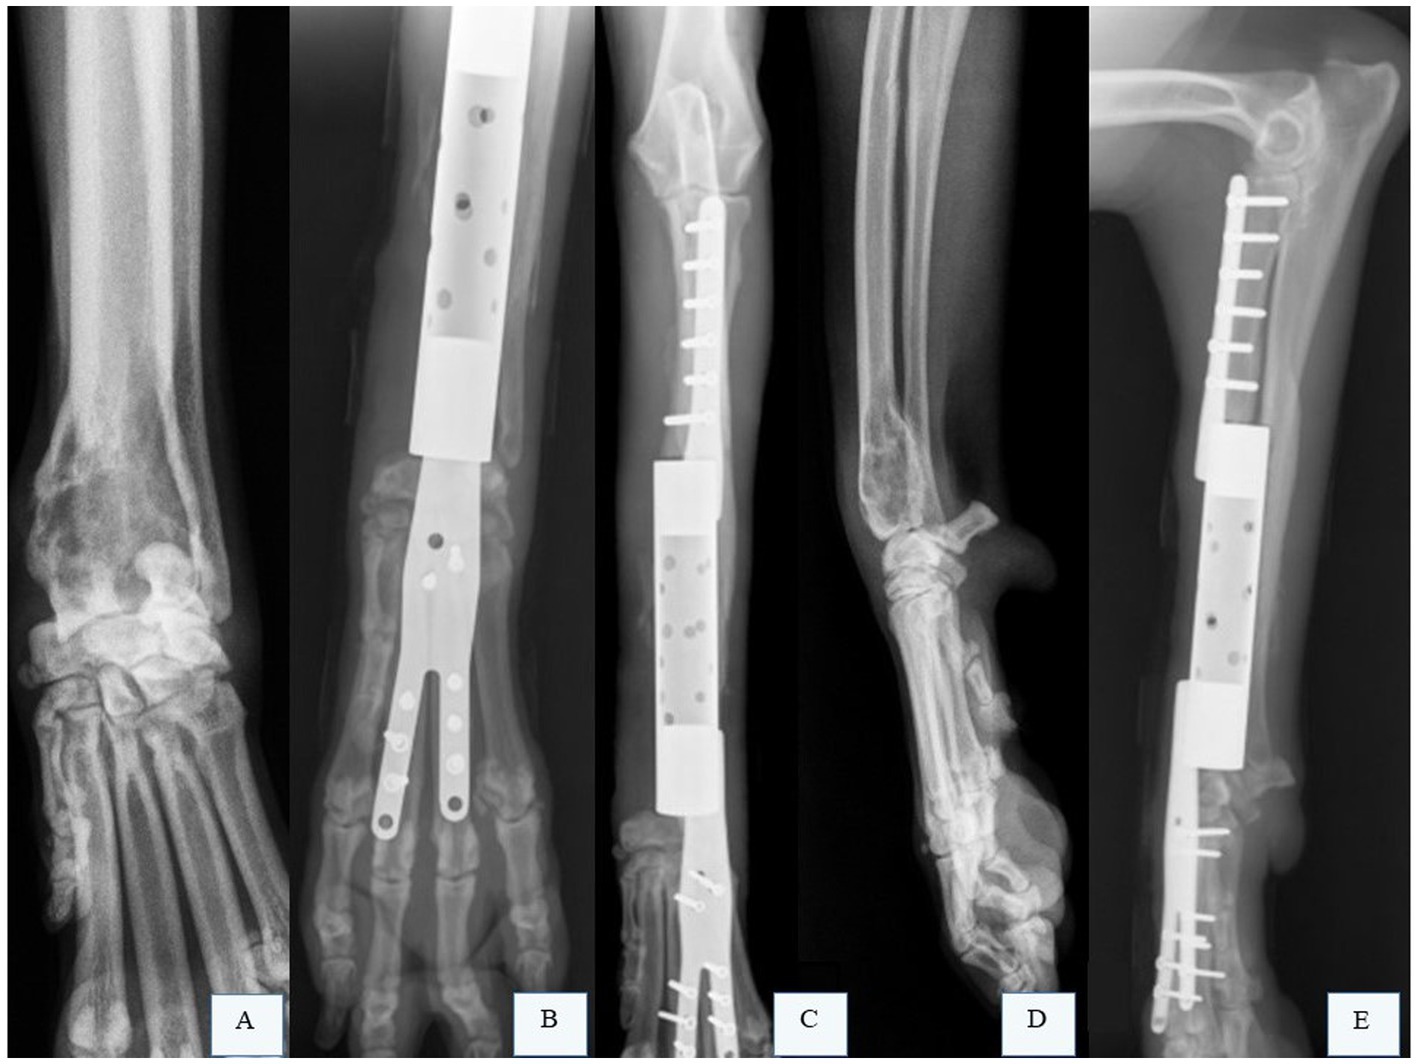

Figure 5

X-ray images of a forearm show different views with orthopedic hardware. Panels A and C display a pre-surgical view of the arm. Panels B, D, and E show post-surgical lateral, frontal, and side views, respectively, with metal plates and screws stabilizing the bone.

Figure 5. Radiographic images of the right radius and ulna of a canine patient with osteosarcoma (OSA) that underwent limb preservation surgery and reconstruction with a patient-specific titanium endoprosthesis. (A) Radiographic image in the craniocaudal projection of the right radius and ulna of a canine patient with OSA in the distal radius. (B,C) Radiographic images of the right radius and ulna after limb-sparing surgery with partial ulnar resection and reconstruction using a patient-specific titanium endoprosthesis. (D) Radiographic image in the mediolateral projection of the right radius and ulna of a canine patient with OSA in the distal radius. (E) Radiographic image of the right radius and ulna after limb-sparing surgery with partial ulnar resection and reconstruction using a patient-specific titanium endoprosthesis. Courtesy of Dr. Eduardo Capasso dos Anjos Afonso; none of the images have been published in any other scientific work.